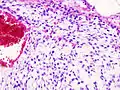

Histopathologic image of chondrosarcoma of the chest wall. Surgical resection of recurrent mass. H & E stain.